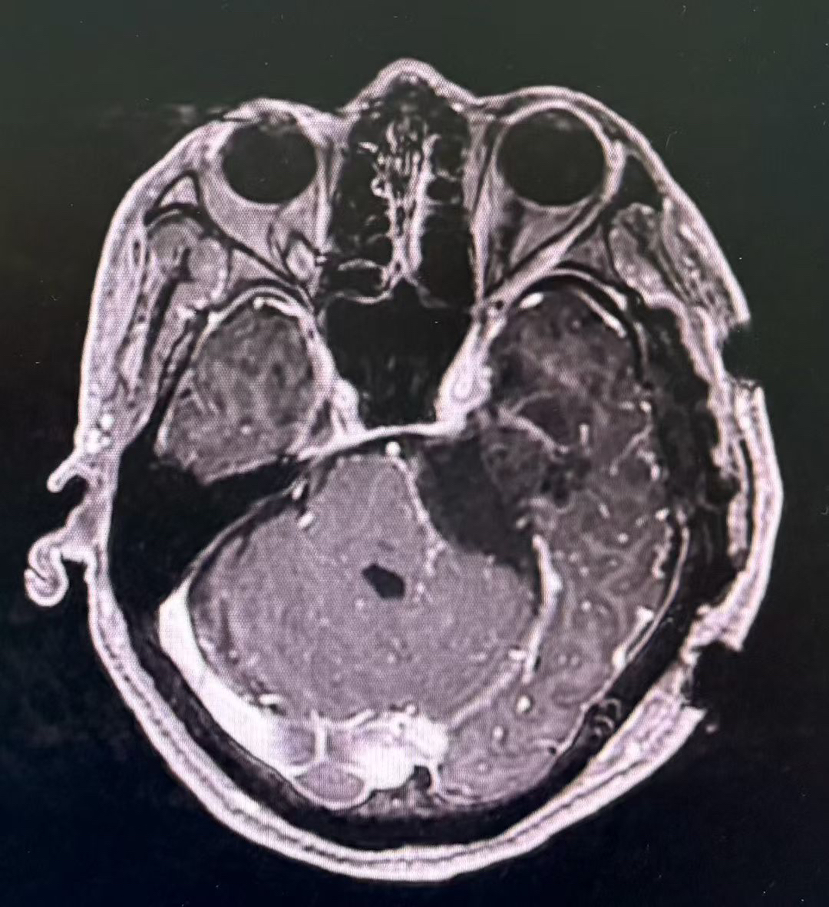

术前MRI

术后MRI